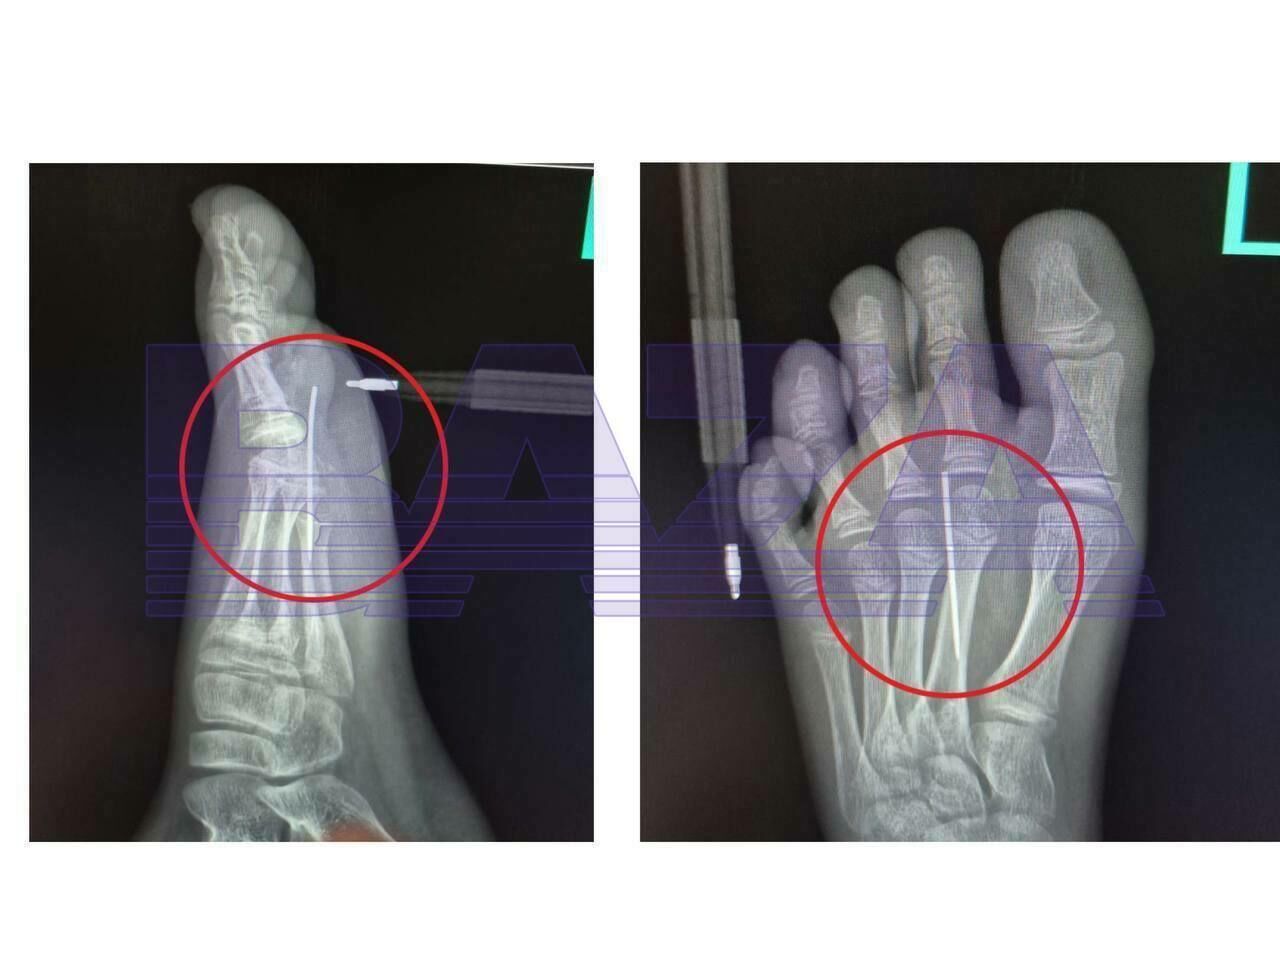

Как сообщает Telegram-канал BAZA, юного пострадавшего доставили в Красногорск, где показали врачам одного из медучреждений. Специалисты извлекли иглу с помощью специального инструмента.

Фото: Telegram / BAZA